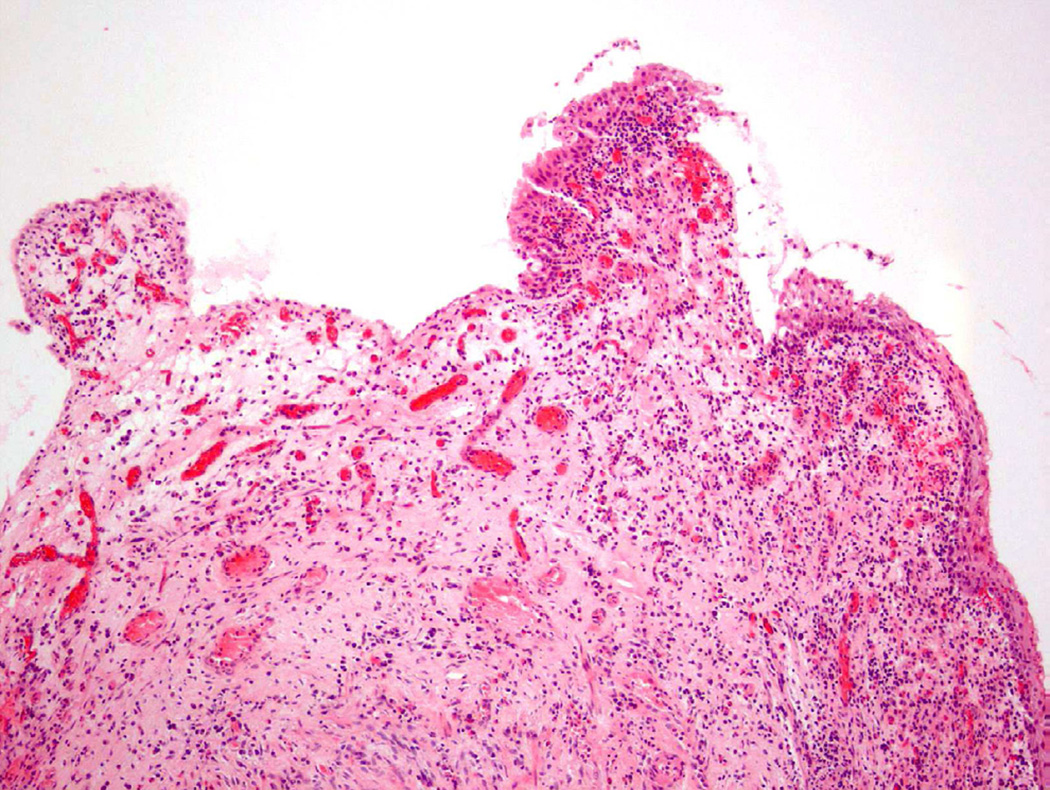

Polypoid Cystitis

Polypoid cystitis, a common variant of cystitis in the bladder, remains a challenging inflammatory lesion for pathologists and urologists alike13 (fig 7). On cystoscopy, the often exophytic growth pattern of polypoid cystitis may clinically resemble a papillary neoplasm. These lesions tend to appear in patients with a history of indwelling catheters, fistulas, chronic obstruction, or calculi. Microscopically, the lesion consists of large, bulbous outpouchings of the urothelial lining, with the lamina propria often quite edematous (Fig. 8)13. Over time, ongoing inflammation may produce scarring of the lamina propria leading to a more papillary-like appearance, as well as induce squamous metaplasia and reactive atypia14. In a 2008 study, 41 cases of polypoid cystitis that had been previously misdiagnosed as papillary urothelial neoplasia were re-reviewed13. Despite some mild atypia and mitotic figures in many of the cases, the cytologic features included uniform cell enlargement, similar vesicular chromatin patterns, and a single prominent nucleolus. Each of the 41 cases lacked definitive hyperchromasia and nuclear pleomorphism which are key criteria in differentiating benign, reactive lesions from neoplasia.

Figure 7.

Polypoid cystitis.